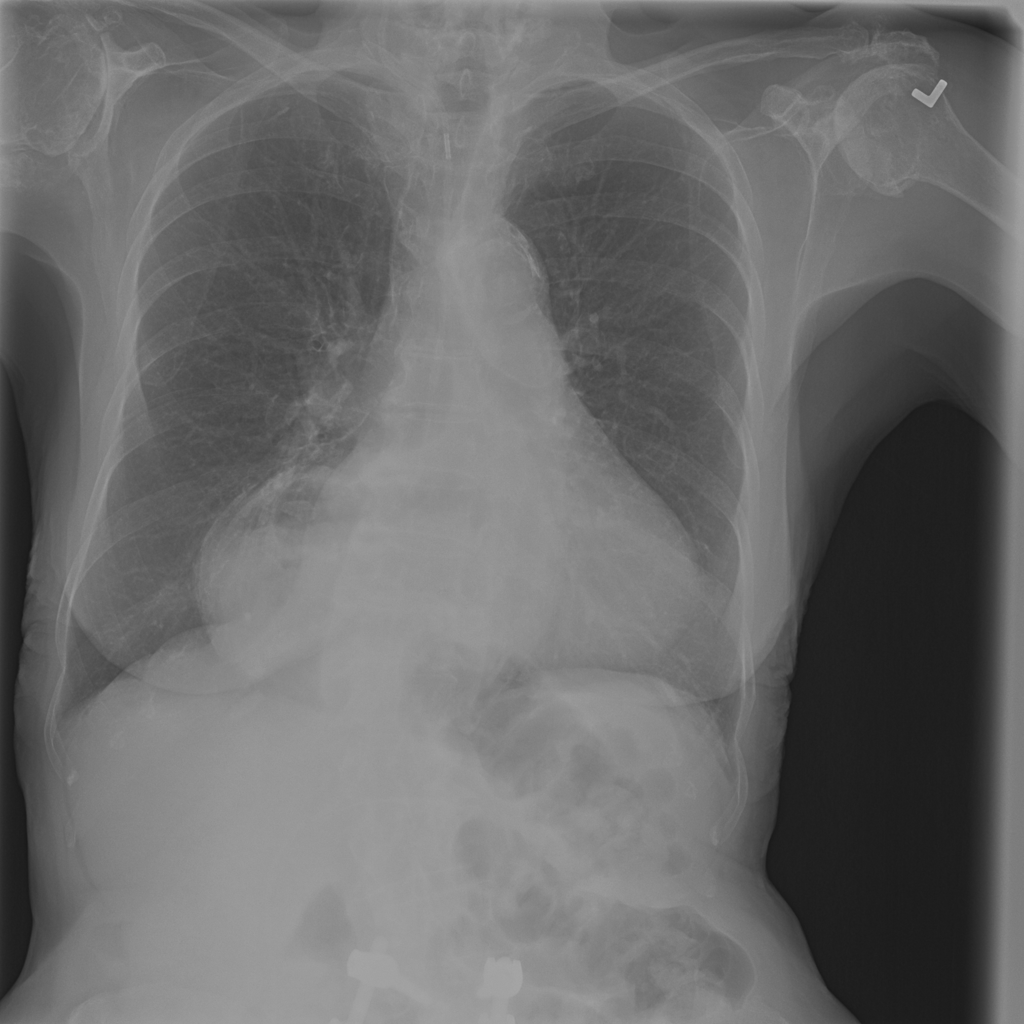

PAT-0ABD · IMG-000Hernia

PAT-0ABD · IMG-000

PA